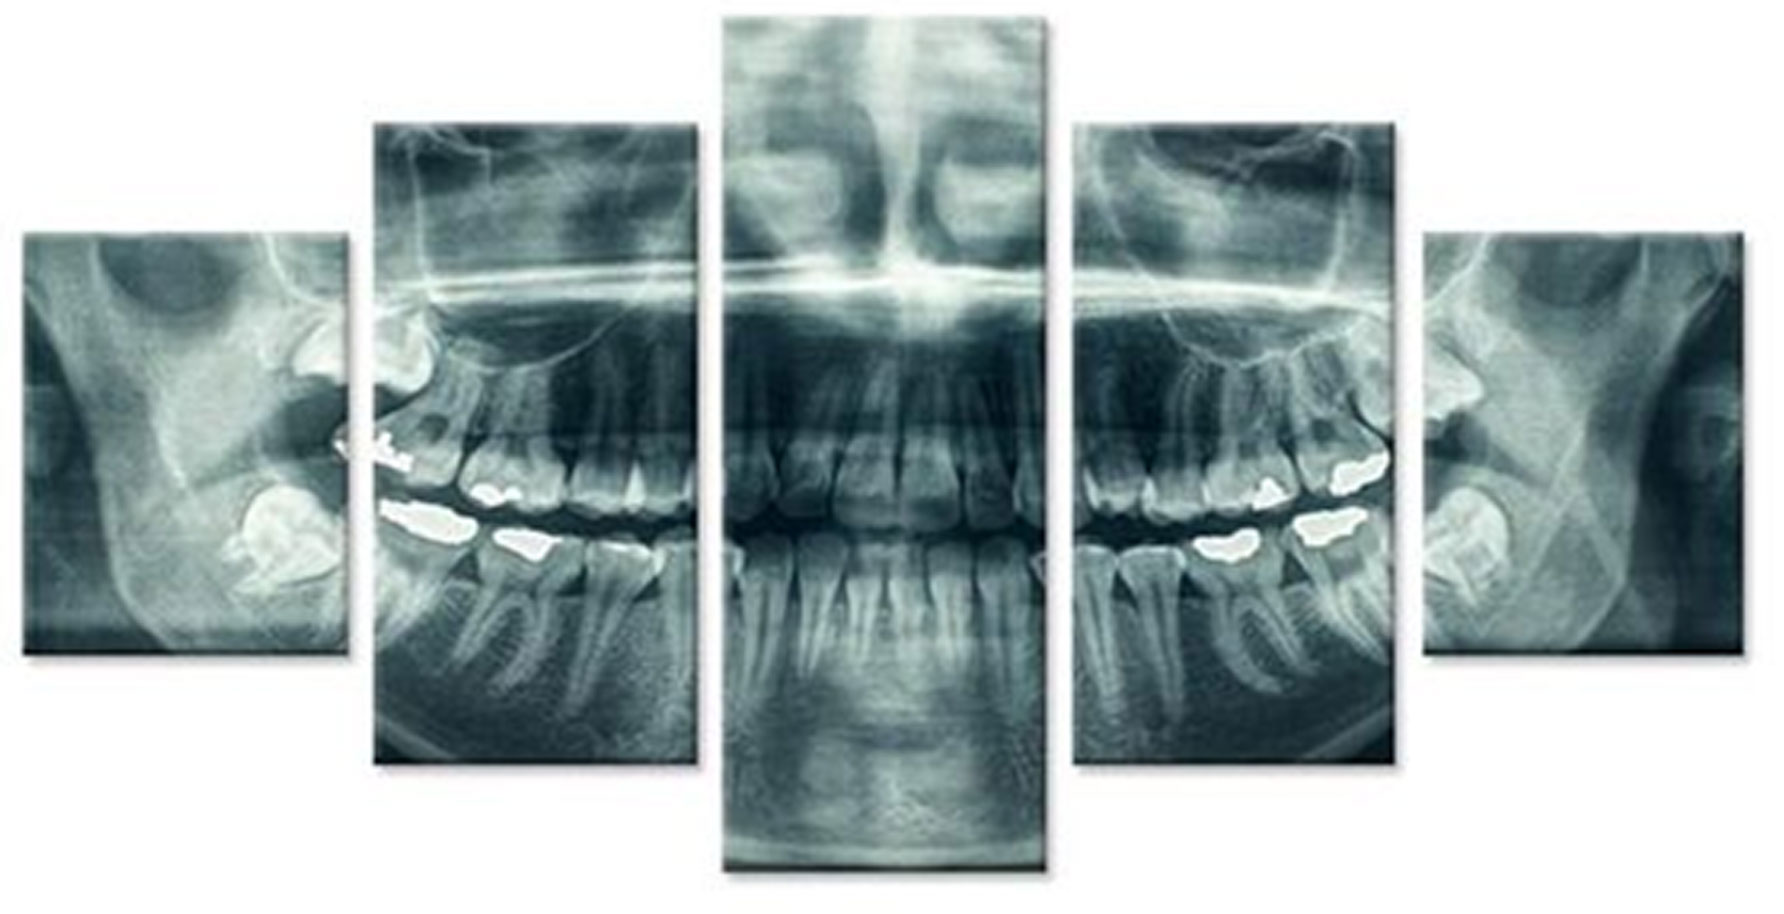

За точна дијагноза и третман насочен кон целта, потребно е да се погледне во внатрешноста на забот. За таа цел нудиме широк спектар на опции за оваа намена.

Преку нашите истражувачки активности, нашиот тим е запознаен со најновите научни наоди и може да ги исполни највисоките технолошки и професионални очекувања. За прегледи и проценки, имаме широк спектар на опции. Користиме различни методи за сликање, како што се проекциона радиографија, томографија и компјутерска томографија.

Kористиме најнова технологија за да овозможиме прецизен третман за нашите пациенти преку методи на снимање.